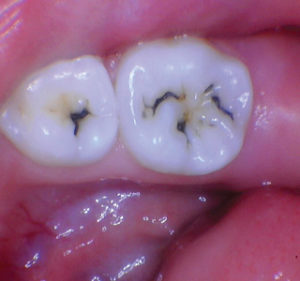

Figura 1 Vista preoperatoria del primer molar primario superior. |

Caso 1

Un paciente de 8 años presentó descomposición de OD en un primer molar primario con síntomas de pulpitis reversible. El diente fue el tratamiento planificado para una restauración de OD con Activa Bioactive Restorative (Pulpdent). Tras la excavación por descomposición, se produjo una exposición pulpar que requirió una pulpotomía terapéutica. Debido a la edad del paciente, me sentí cómodo con una pulpotomía terapéutica con Biodentine (Septodont) seguida de una restauración estética. Si el paciente hubiera tenido entre cuatro y cinco años, me habría restaurado con una corona de acero inoxidable debido a su historial comprobado de longevidad.